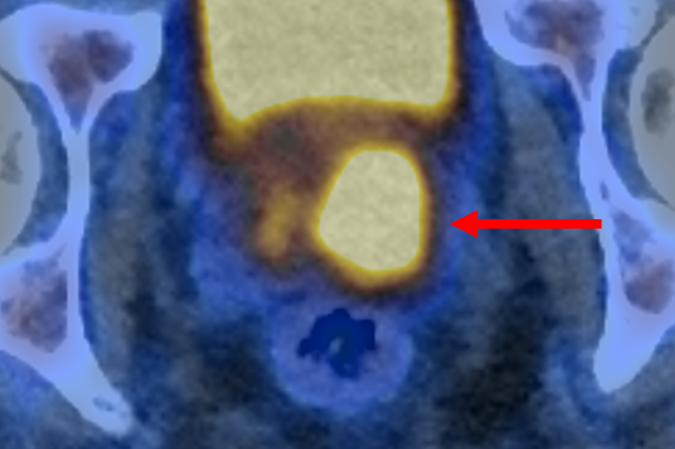

O exame PET/CT (tomografia por emissão de Pósitrons/tomografia computadorizada) com PSMA identifica células agressivas presentes na próstata, que são potencialmente prejudiciais e podem precisar de tratamento. Isso é possível graças a uma molécula que se liga a essas estruturas e as faz brilhar, aparecendo como pontos luminosos na imagem. O estudo afirma que isso também pode ajudar a reduzir o risco de sobrediagnóstico.

O ensaio descobriu que a tomografia por emissão de pósitrons (PET/CT) com PSMA podia identificar pessoas que não tinham câncer ou cujo tumor era de tão baixo risco e com crescimento tão lento que provavelmente nunca causaria danos. Esses pacientes não precisaram de biópsia. A nova abordagem reduziu pela metade o número de pessoas submetidas ao exame invasivo, sem deixar de detectar nenhum câncer maligno.

A abordagem também beneficiou os pacientes que ainda precisavam de biópsia. Os resultados da tomografia garantiram que o procedimento fosse direcionado às áreas suspeitas identificadas no exame de imagem, a fim de minimizar complicações e aumentar a precisão.